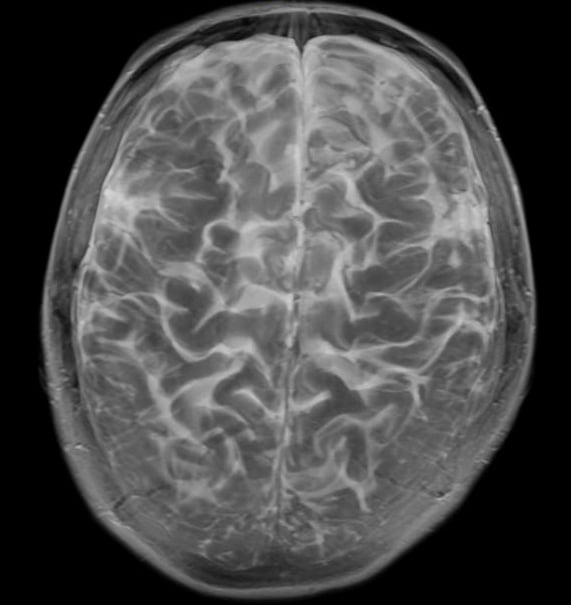

MRI scans may be able to detect physical and functional changes in the brain that could be markers for major depression. But we have managed to identify a network of brain regions that is affected in people with depression raising hope that brain scans could soon be used to diagnose it.

Brain imaging can also rule out a direct physical cause like a tumor or a brain bleed of psychiatric symptoms. It turns out depression is not a cookie cutter disease but a range of brain dysfunctions that lead to varying symptoms. Researchers have uncovered specific brain.

Brain scans can detect signs of depression and anxiety People with depression and anxiety have a common pattern of brain abnormalities that can. Depression brain scans including PET scans and MRIs for depression can provide images of the brain of someone with depression or another mental health disorder. The brain can definitely do some freaky things at times.

By comparing depression brain scans to the scans of people without depression researchers can look for similarities and differences in an effort to gather more information. Depression may be patterned to certain underlying brain structures. Brain scans can show evidence of the root cause of your depression.